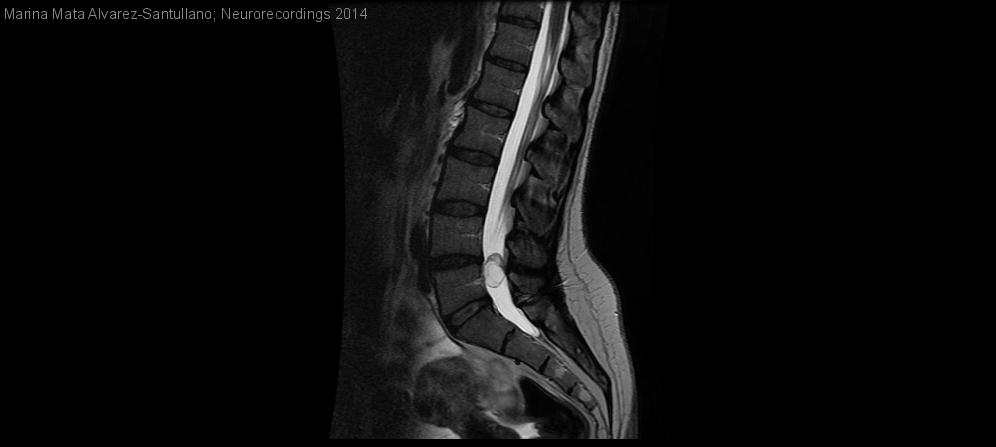

Quiste en espacio subaracnoideo lumbar como causa infrecuente de lumbociática

Mujer | 44 años

Diagnóstico final: Ependimoma mixopapilar lumbar